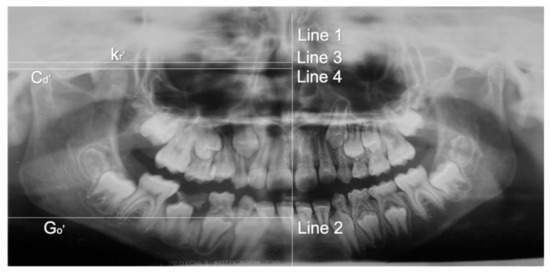

2. Clinical Case